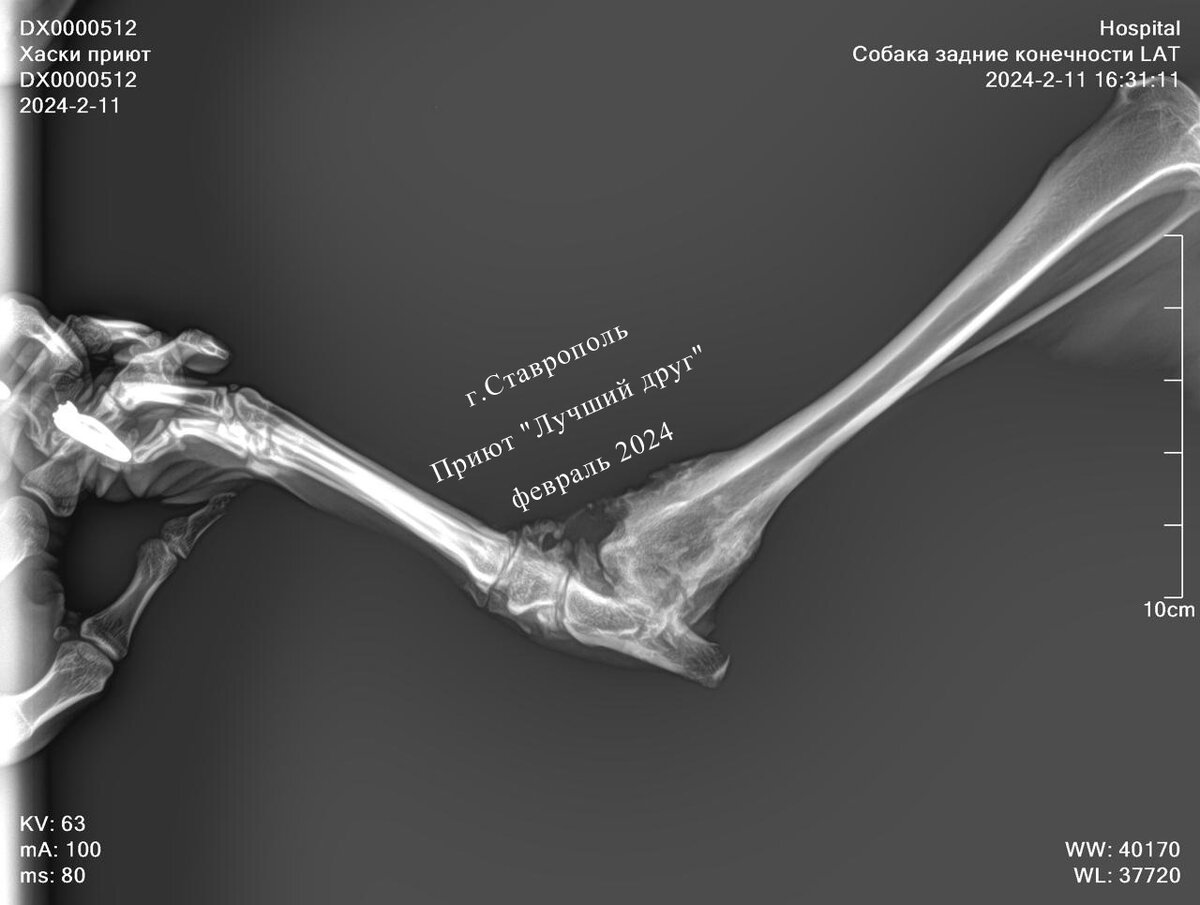

Симпатичного доброго парня с голубыми глазами нашли в Кочубеевском. На лапу не опирается, рана несвежая, инфицированная. Привезли красавца в Ставрополь в клинику. По рентгеновскому снимку перелом скакательного сустава, но, к сожалению, травма слишком старая, оперировать смысла нет. Будет приспосабливаться жить с кривой конечностью. Несколько дней пёс Джеки пробыл на стационаре, рану ему зачистили, обработали и выписали в приют. Жизнерадостный пес, которому не повезло родиться породистым, а по итогу оказаться на улице никому ненужным... Очень хочется призвать к ответу разведенцев, но кто станет прислушиваться к приютам и волонтерам, если нет законов, регулирующих разведение собак. Когда бесконтрольно плодят никому не нужных щенков, распродают за копейки, нимало не заботясь о судьбе этих животных.

Симпатичного доброго парня с голубыми глазами нашли в Кочубеевском. На лапу не опирается, рана несвежая, инфицированная. Привезли красавца в Ставрополь в клинику. По рентгеновскому снимку перелом скакательного сустава, но, к сожалению, травма слишком старая, оперировать смысла нет. Будет приспосабливаться жить с кривой конечностью. Несколько дней пёс Джеки пробыл на стационаре, рану ему зачистили, обработали и выписали в приют. Жизнерадостный пес, которому не повезло родиться породистым, а по итогу оказаться на улице никому ненужным...